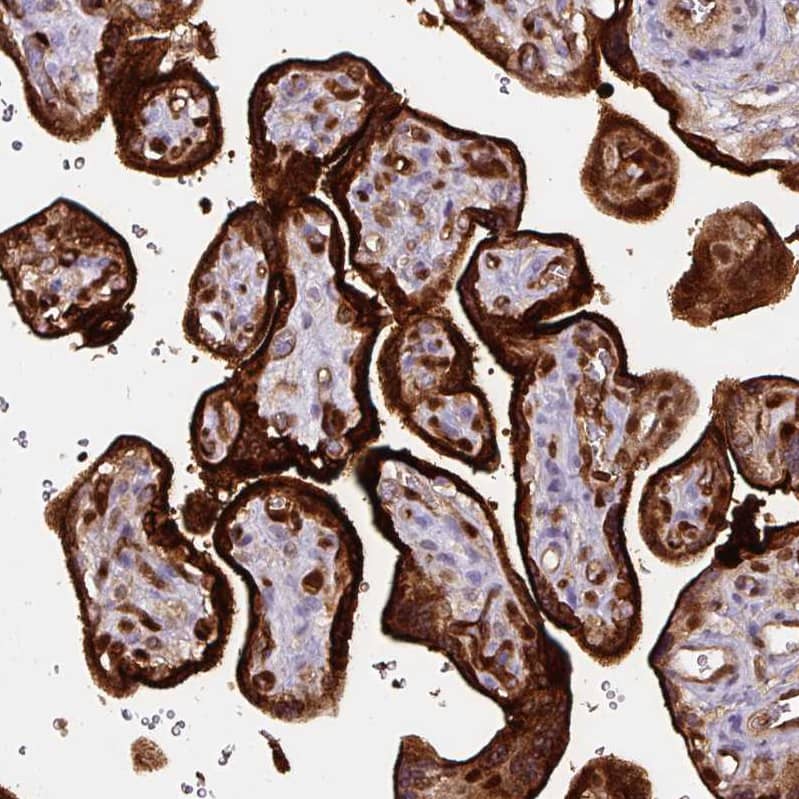

Staining of human placenta shows strong immunoreactivity in the trophoblastic cells.